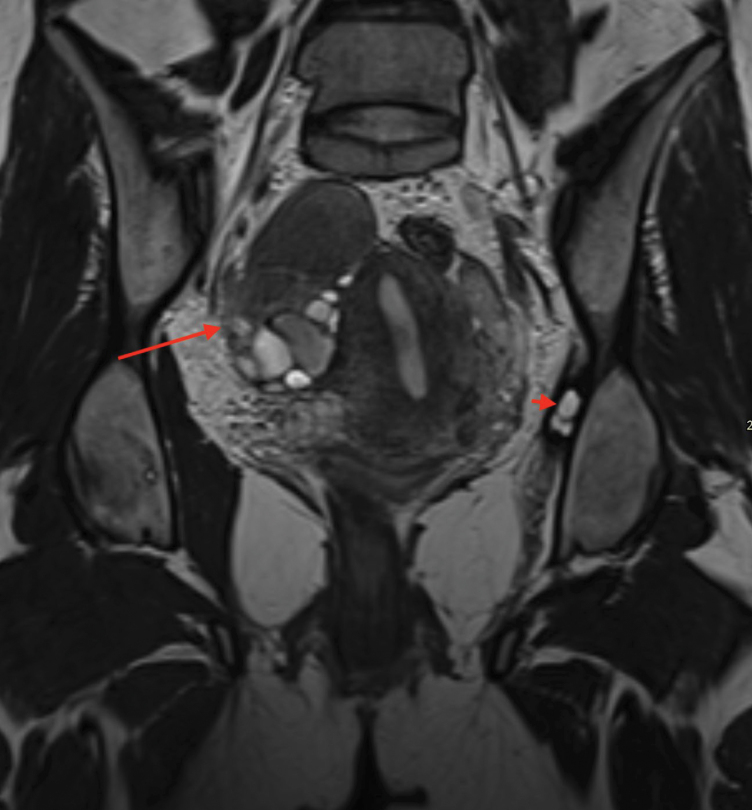

Extrapelvic Endometriosis Involving Pudendal and Sciatic Nerve Causing Obturator Muscle Atrophy.

Teaching point: Extrapelvic endometriosis involving pudendal and sciatic nerve may be a cause of lower limb pain.